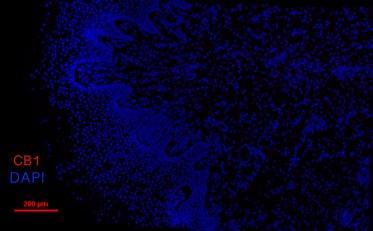

The image on the cover shows immunofluorescence image showing labeling of Cannabinoid type 1 (CB1, red) receptors in the basal and upper layers of the NHP vaginal epithelium. (See page 67 by Rachel Shaw.)

Visualizing CB1 Receptors in Vaginal Epithelium of Nonhuman Primates

Rachel Shaw 1, Katrina Knight1,2 and Pamela Moalli1,2

1Department of Bioengineering, University of Pittsburgh.

2Magee-Womens Research Institute & Foundation.